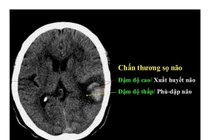

(khoahocdoisong.vn) - Chấn thương sọ não nặng được điều trị bằng phẫu thuật, hồi sức hoặc phối hợp. Kết quả hồi sức và điều trị bệnh nhân chấn thương sọ não nặng phụ thuộc vào nhiều yếu tố như tuổi, tình trạng bệnh nhân, tổn thương tại não, tổn thương phối hợp, thời điểm điều trị.

(khoahocdoisong.vn) - Chấn thương sọ não thường bắt nguồn từ các loại chấn thương về não bao gồm chảy máu, chấn động mạnh, rung động não hoặc não bị bầm.